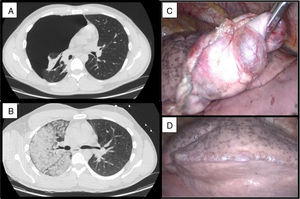

Varón de 28 años, que tras 5 días con dolor pleurítico es diagnosticado, mediante TAC de tórax, de neumotórax completo derecho. Tras inserción de drenaje pleural 10F, conectado a −20cm H2O, el paciente comienza con tos irritativa, dolor centrotorácico, hipotensión, taquicardia y desaturación. Se estabiliza al paciente en la UCI, solicitándose nuevo TAC que muestra opacidades en vidrio esmerilado en pulmón derecho, compatible con edema por reexpansión pulmonar (fig. 1). El paciente no mejora y precisa conexión a ventilación mecánica invasiva. Tras 48h se consigue la extubación. En la cirugía se objetivaron lesiones bullosas apicales y múltiples blebs, realizándose bullectomía y pleurodesis mecánica por videotoracoscopia con retirada del drenaje pleural y alta a las 72h de la cirugía, sin complicaciones.

El edema de reexpansión pulmonar, descrito por primera vez en 1853 por Pinault, es una complicación rara, generalmente inferior al 1%, que surge tras una rápida reinsuflación del pulmón por la evacuación de un neumotórax o derrame pleural. Alcanza cifras de mortalidad del 20%1. El diagnóstico es clínico, apoyado en pruebas de imagen. Su tratamiento radica en medidas de soporte, requiriendo CPAP o incluso VMI con PEEP en los casos más severos, como el nuestro. La sospecha clínica para actuar diligentemente es fundamental2.